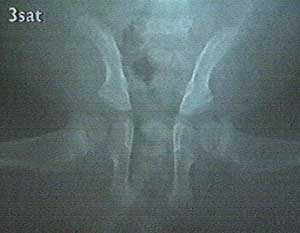

Even worse, a few weeks later Anton could not stand up anymore. X-ray showed that he had a pelvis symphsis, the femur joints not longer being fixed in their sockets, [pic 19] which might have been caused by the wet and slippery box floor during his first weeks. He got a corset and spent some hours daily in a kind of narrow box to strengthen the tissues. [pics 20-21] And then Anton got an strong angina and hardly survived.